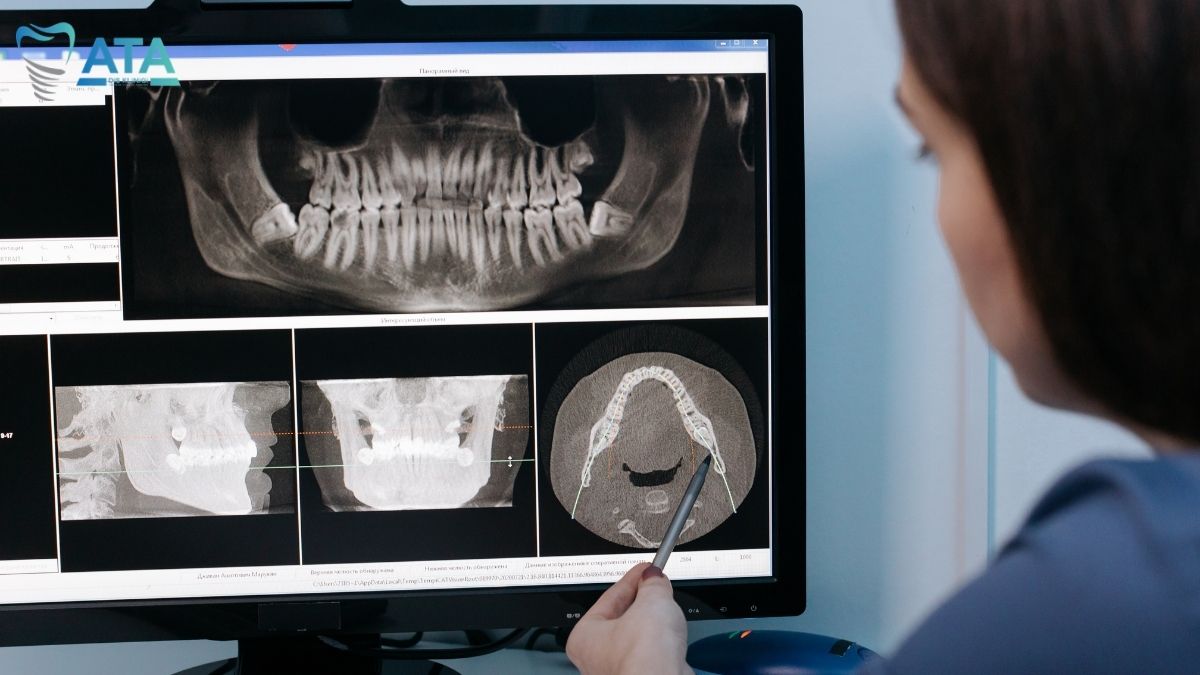

Diş çekimi öncesinde, hastaya kapsamlı bir ağız içi muayene uygulanır ve gerekli görülen durumlarda radyografik (röntgen) görüntüleme yapılır. Dişin pozisyonu, kök şekli ve çevre anatomik yapılar alanında uzman hekim tarafından ayrıntılı şekilde değerlendirilir. Muayene sonucunda, hastaya planlanan diş çekimi prosedürü hakkında bilgilendirme sağlanır. Gömülü diş gibi cerrahi müdahale gerektiren durumlarda ise, ilgili cerrahi planlama titizlikle oluşturulur.

20’lik Diş Cerrahi Çekim

Gömülü veya kırık dişlerde cerrahi çekim uygulanır. Lokal anestezi altında steril koşullar altında gömülü diş çekimi yapılır. Yöntem, komplikasyon riskini en aza indirir.